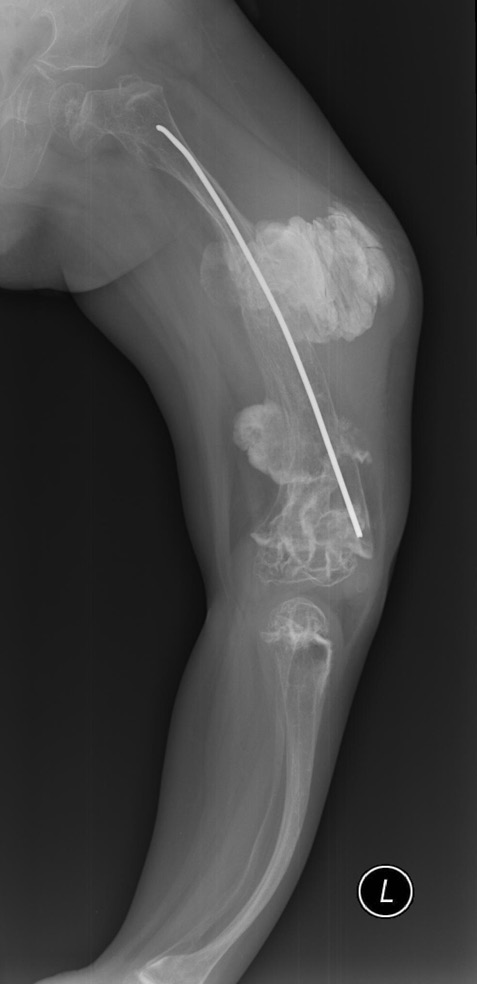

OI diagnosis is based on clinical signs and anamnestic data–fractures in the perinatal age or high incidence of fractures among relatives. Genetic testing is used to diagnose milder forms of OI, when patients do not have characteristic phenotypic signs but are susceptible to fractures [17]. In some countries, genetic research is used to eliminate child violence in the family as a possible cause of frequent fractures. Thus, according to a study, 11 of 262 fractures in children were presumed to be caused by child abuse in the USA. Based on the results of a genetic study, OI was detected in six of them [18]. OI type is determined by a combination of these data in accordance with the classification given in the article Nosology and Classification of Genetic Skeletal Disorders and according to genetic analysis data. Determining the OI type is important to assess disease severity, predict the possible complications of surgical treatment, and choose the most effective drug treatment. Thus, in patients with OI type V, the probability of hypertrophied callus formation after surgical treatment is high (Fig. 1) [10, 11]. Understanding the genetic mechanisms of OI development opens up prospects for targeted treatment. For example, intravenous administration of bisphosphonates in patients with OI of type VI is less effective than the use of denosumab [19].

Fig. 1. Hypertrophic callus after surgical treatment of a patient with type V osteogenesis imperfecta